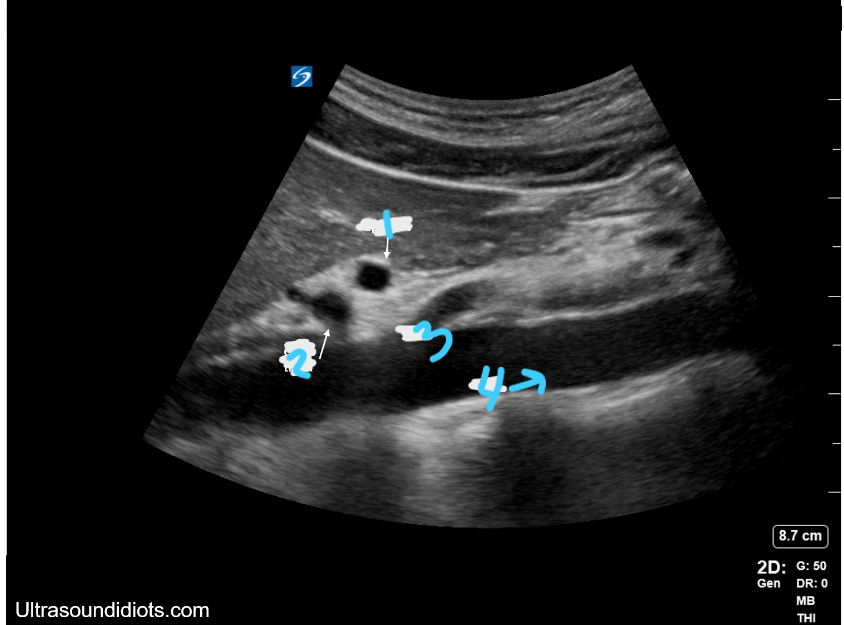

<p>In this sagittal view, what is #1?</p>

In this sagittal view, what is #1?

Splenic Vein

<p>In this sagittal view, what is #2?</p>

In this sagittal view, what is #2?

Celiac Trunk

<p>In this sagittal view, what is #3?</p>

In this sagittal view, what is #3?

SMA

<p>In this sagittal view, what is #4?</p>

In this sagittal view, what is #4?

Aorta